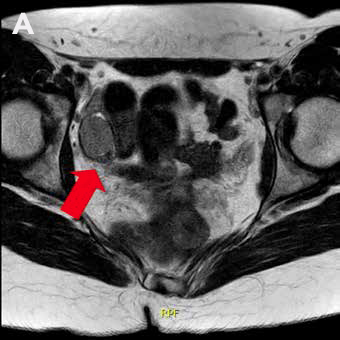

La RM de abdomen y pelvis (Figura 1) demuestra agenesia uterina y ausencia de gran parte de cavidad vaginal, reconociendo 2 nódulos de aspecto solido homogéneos en excavación pélvica (posición anexial) con señal sugerente de testículos, con diámetro mayor de 31 mm a derecha y de 21 mm a izquierda.